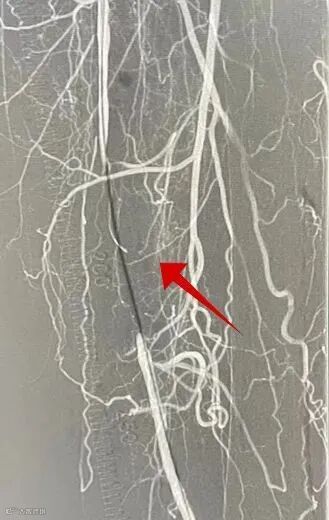

分离器抓取到大块陈旧血栓

股浅动脉恢复通畅,球扩后造影见左侧胫腓干动脉栓塞,考虑栓子脱落。

送入抽吸导管抽吸数秒,造影提示胫腓干恢复通畅。